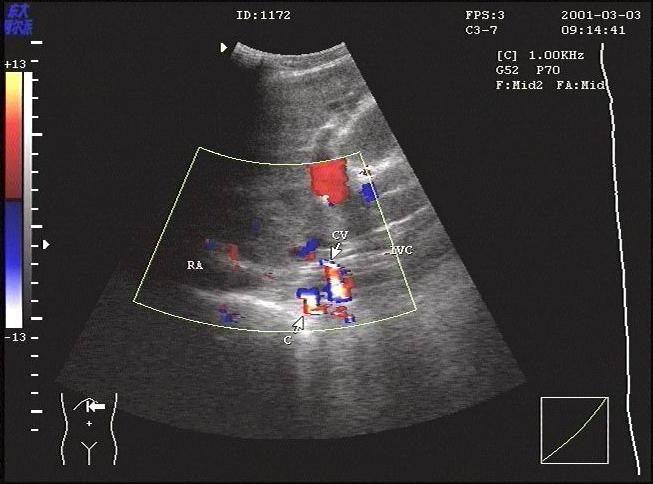

B超工作站/超声工作...